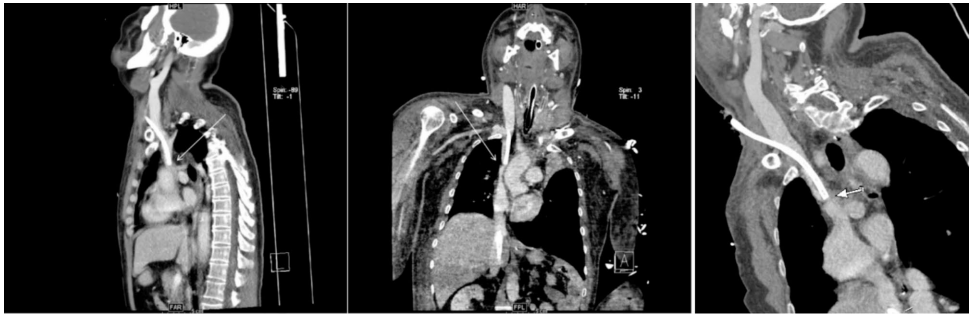

术前CT血管重建显示SVC入心处成角(图3)

ECMO期间增强CT证实导管尖端对应位置SVC狭窄(图2/4)

通过对比术前/术中CT,首次捕捉到ECMO导管加剧SVC成角至功能性狭窄的动态过程。三维曲面重建(CPR)技术直观显示导管与血管壁的机械性冲突。